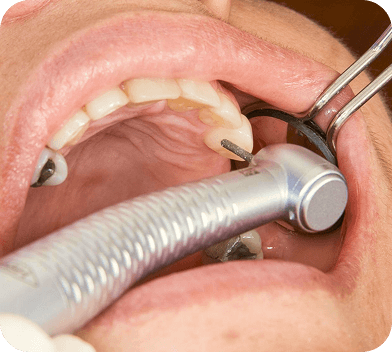

A raspagem é indicada para remover tártaro e placa bacteriana que se acumulam abaixo da gengiva, evitando inflamações e retrações. O procedimento é rápido e seguro, e ajuda a manter a gengiva firme e saudável.